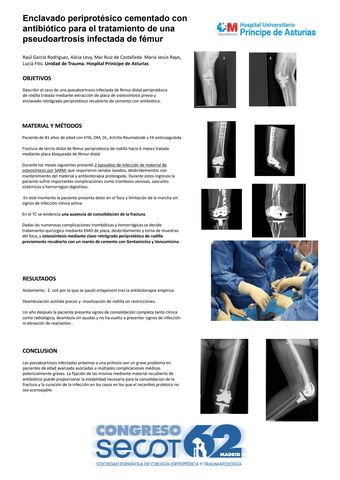

Enclavado periprotésico cementado con antibiótico para el tratamiento de una pseudoartrosis infectada de fémur

RAUL GARCIA RODRIGUEZ, MARÍA JESÚS RAYO NAVARRO, MAR RUIZ DE CASTAÑEDA , ALICIA LEVY BENGUIGUI, LUCÍA FITO JORDÁN